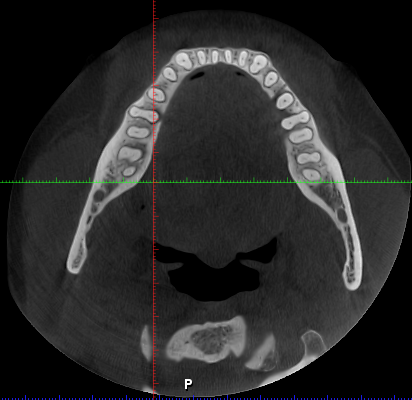

- FOV medio→ una arcada (10cm x 5’5cm, 13cm x 5’5cm) o bimaxilar (10cm x 9cm, 13cm x 9cm)

- Implantes: FOV medio o localizado según la zona